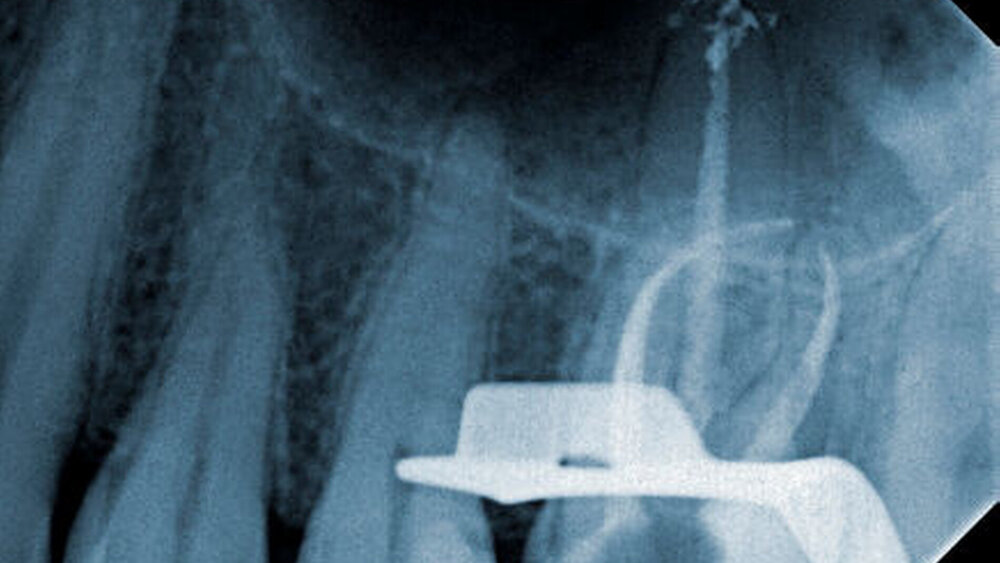

Nach Übernahme des Patienten und unter Zuhilfenahme eines mobilen Dentalmikroskops wurde zunächst der koronale Wurzelkanalanteil erweitert, um den Umgehungsversuch zu ermöglichen. Anschließend wurde probiert, mittels vorgebogener Stahlfeilen das apikal gelegene Bruchstück zu passieren. Dies gelang unerwarteterweise relativ zügig und unkompliziert. Unter endometrischer Kontrolle konnte die Arbeitslänge ermittelt werden. In Absprache mit dem Patienten sollte nun doch die Fragmententfernung mithilfe der Braiding-Technik versucht werden [Gilbert and Rice, 1987].

Hierbei werden zwei bis vier K- beziehungsweise Hedströmfeilen neben dem Fragment positioniert. Anschließend werden diese Feilen verdrillt, um die Spannung zum Fragment zu erhöhen. Durch Zugkraft kann dann das eingeklemmte Fragment geborgen werden. Dieses Verfahren ist jedoch riskant, es besteht die Gefahr der zusätzlichen Fraktur der eingebrachten Stahlfeilen, wenn diese zu weit ins Wurzelkanalsystem eingedreht werden. Vor dem Bergungsversuch empfiehlt es sich, die übrigen Wurzelkanaleingänge (beispielsweise mit Watte) abzudecken, um ein Verlagern des gelösten Fragments in andere Wurzelkanalanteile zu verhindern. In diesem Fall gelang die Positionierung von zwei Hedströmfeilen neben dem Bruchstück und bereits nach wenigen Versuchen konnte das Fragment vollständig entfernt werden (Abbildung 3).

Das Bruchstück schien somit nur leicht im Wurzelkanalsystem verklemmt gewesen zu sein. Die anschließende Instrumentation, Desinfektion und thermoplastische Obturation gelang ohne weitere Komplikationen (Abbildung 4).